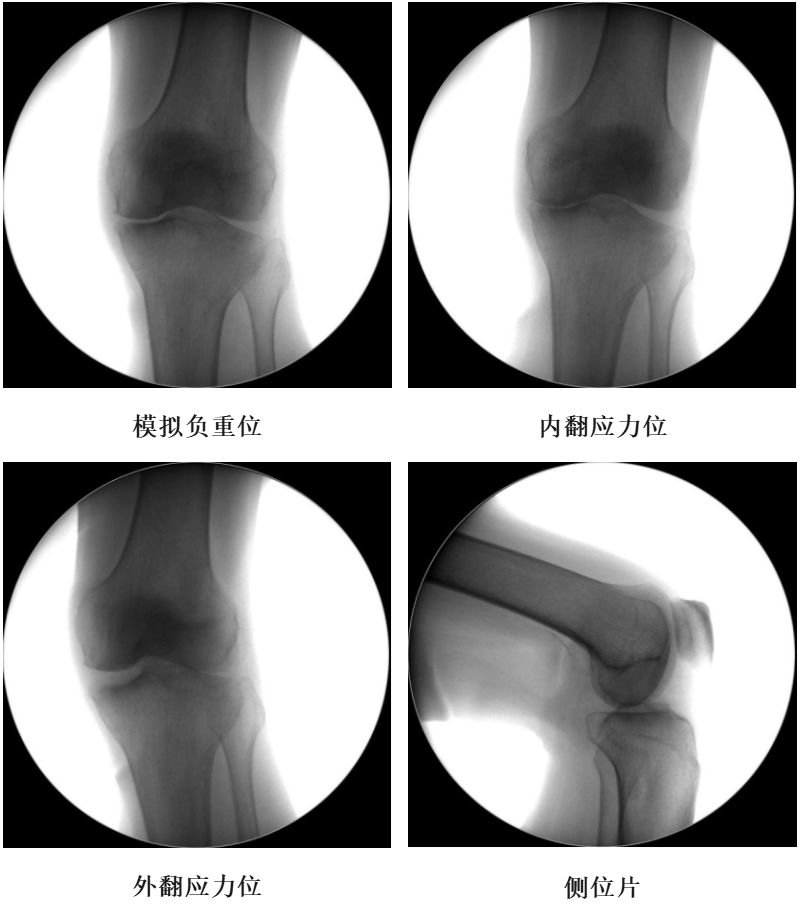

术前透视片

四、术后X透视片